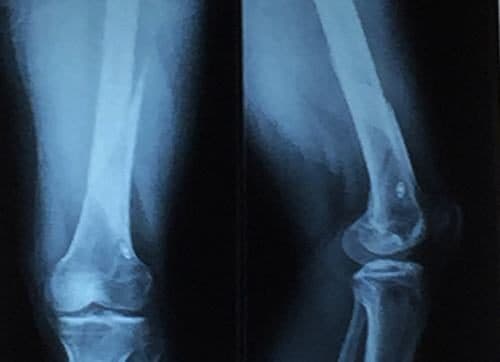

Chụp X quang khớp gối

Một số bệnh lý ở khớp gối cần chụp X quang thường gặp

Bệnh thường gặp ở người già cùng với quá trình lão hóa của cơ thể. Ở giai đoạn sớm, khớp gối chưa hưu hại ngay, chỉ đến khi dịch khớp bị hao hụt thì độ ma sát giữa các đầu khớp mới tăng lên và làm sụn khớp bị ăn mòn làm hẹp khe khớp gối. Lâu dần, nếu không điều trị sẽ ăn mòn đến xương làm phá hủy mô xương, chụp X quang gọi là gai xương.

Khớp gối có bốn dây chằng chính giúp giữ xương với nhau và để khớp gối được ổn định. Các vấn đề như giãn dây chằng, rách đứt dây chằng cũng ảnh hưởng trực tiếp đến khả năng vận động của khớp gối.